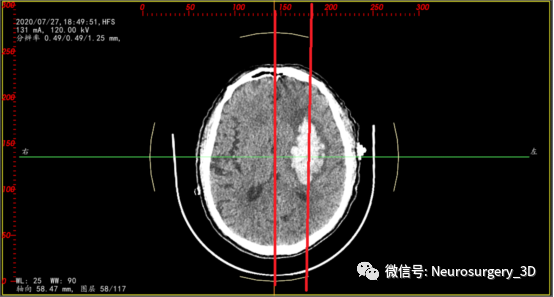

两天后的CT复查(2020年7月30日9:46)并测量不同区域的CT阈值,三维重建阈值选择45-100,包含低密度血肿区域。

是活动性出血吗?对比脑部活动性出血CT征象,一些文献报道:CT混杂征是由Li等在2015年提出的一种预测血肿扩大的影像标记,主要是指(1)血肿内存在边界分明的高低密度两种成分,(2)两种成分CT值至少相差18HU,且(3)低密度成分不包含于高密度成分中的一种征象。其形成的机制是血肿内凝固的血块在CT上呈现高密度,而低密度区域可能是由于破裂的血管仍在持续出血,血液尚未凝固所致。(下符CT混杂征片)

对比上述文献1、2、3还真像活动性出血,血肿较前两次CT检查又有增大现象,如果考虑活动性出血,手术方案无疑选择开瓣血肿清除了,年龄、身体耐术力、基础疾病等种种影响因素都是在活动性出血因素之后考虑的次要因素。

我中心近年来多次遇到这种CT征象:1、血肿内存在界限分明的高密度区域和低密度区域,且低密度区域呈半包围于高密度区域;2、多次CT复查,高密度血肿增加不明显,血肿扩大为低密度血肿;3、一般初次CT检查是高密度血肿,2-3天后血肿体积扩大,扩大的血肿为低密度血肿,高密度血肿无扩大。其形成机制考虑为长期饮酒或口服抗凝药物后,脑部小血管破裂出血致血肿凝固析出渗液,低密度血肿所含血清成分较多,为不凝液状态。这种形态血肿微创穿刺治疗血管比较理想,手术也证实,在微创手术中液态部分能较容易引出,起到迅速减压,缓解颅内压力的目的。

为了验证是不是活动性出血,再次复查颅脑CT(2020年7月30日15:10)如下:两次CT(间隔约6小时)对比,血肿形态无明显变化,证实并非活动性出血。